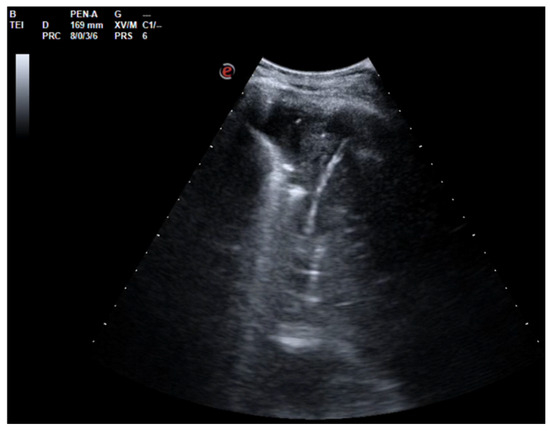

Figure 4. Complex and septated pleural effusion after VATS treated with IPFT.

After a chest CT scan, which showed a massive effusion, the patient underwent a thoracoscopic lavage of the left pleural cavity without any complications. At the end of the surgery, two left thoracic drains were left in place, through which repeated irrigation of the pleural cavity with urokinase was performed under serial US and radiological monitoring in the following days (Figure 4). At the same time, empiric antibiotic therapy with piperacillin/tazobactam and teicoplanin was initiated. During his hospitalization, the patient remained stably apyretic, with a progressive improvement of pulmonary gas exchange and the normalization of his inflammation biomarkers. Subsequently, the FiO2 was gradually titrated until the complete discontinuation of oxygen therapy.

In this scenario, fibrinolysis was performed after a uniportal VATS because of the persistence of fibrinous septa visualized using US and the slow outflow of fluid into the drainage bag. The irrigation of the pleural cavity was conducted with 200,000 UI of urokinase in 50 mL of saline solution. This was followed by the closure of the chest drain for 2–4 h, and then it was reopened. Irrigation was performed every 48 h for 3 days. On day 5, the absence of fibrinous septa and the small amount of fluid on the patient’s chest US allowed for the removal of the drain and his discharge from the hospital.